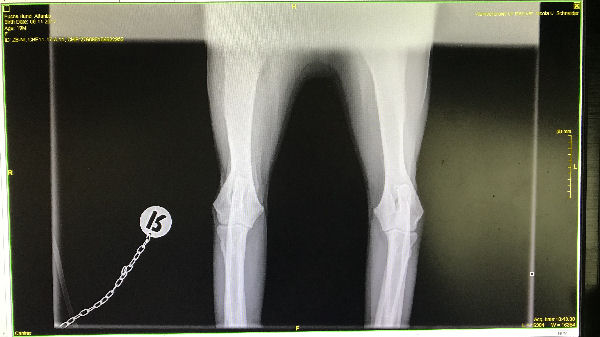

Atlantis - ED-Röntgen

img_5247 (1)-Atlantis-ed-rechts